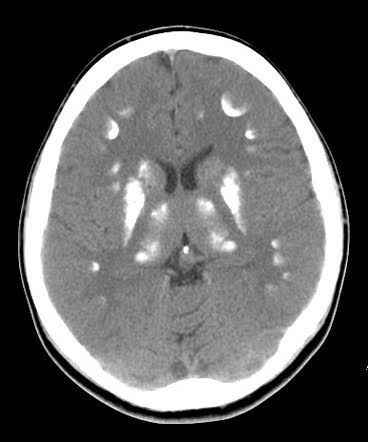

Basal ganglia calcification is a very rare condition that happens when calcium builds up in your brain, usually in the basal ganglia, the part of your brain that helps control movement. Other parts of your brain can be affected as well. This can also be called familial idiopathic basal ganglia calcification or primary familial brain calcification, and it used to be called Fahr’s disease or Fahr’s syndrome. You're most likely to get basal ganglia calcification between the ages of 30 and 60, though it can happen any time. Most people who develop it are in good health before they find out they have it.